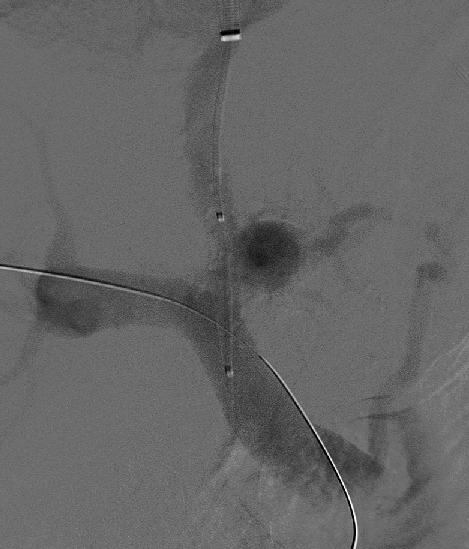

목정맥경유간속문맥전신순환지름술(TIPS)은 문맥과 전신 순환 사이에 새로운 혈관을 연결하여 문맥압을 낮추는 시술이다. TIPS는 시술이 더 쉽고 간의 혈관을 막지 않는다는 장점이 있어, 다른 문맥전신지름술보다 더 많이 쓰이게 되었다.[57] 경경정맥 간내 문맥전신 단락술(TIPS)는 재출혈률을 감소시키는 데 효과적이다.[26][27]

최근에는 혈관 내 치료로서 경경정맥 간내 문맥 정맥 단락술(Transjugular Intrahepatic Portasystemic Shunt: TIPS)이 시도되고 있다. 이는 경부에서 카테터를 삽입하여 문맥과 간정맥을 직접 연결하는 수술이다.

과거에는 개복하여 문맥-하대정맥 단락술 등을 시행했으나, 암모니아 등을 포함한 장관에서의 혈류가 직접 대순환으로 유입되기 때문에 합병증이 나타나는 경우가 있었다.[37] 최근에는 혈관 내 치료로서 목정맥경유간속문맥전신순환지름술(TIPS)이 시도되고 있다. 이는 경부에서 카테터를 삽입하여 문맥과 간정맥을 직접 연결하는 수술이다.[37]TIPS는 시술이 더 쉽고 간의 혈관 분포를 방해하지 않는다는 장점이 있다.[37]